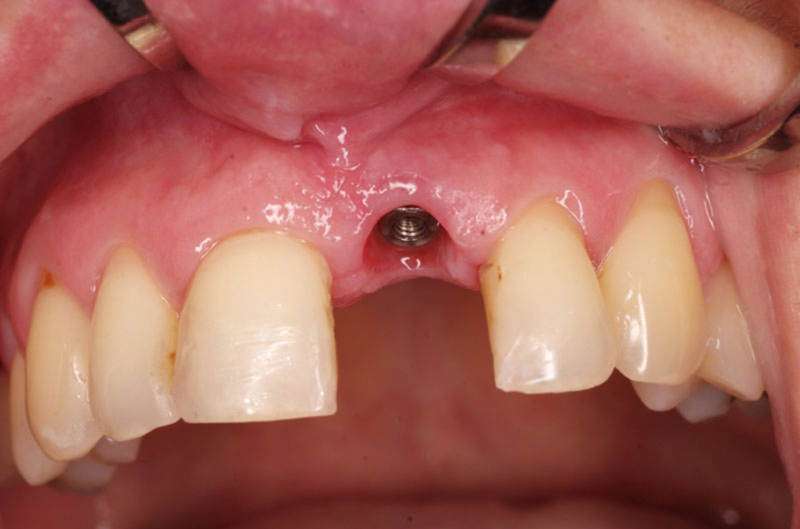

Náhrada jednoho zubu

Klasickým příkladem a indikací pro použití implantátu je ztráta jednoho zubu (v tomto případě v předním – frontálním úseku) v jinak zdravém, nepoškozeném chrupu.

Nejčastější příčinou takové ztráty je sportovní nebo dopravní úraz.

Náhrada jednoho zubu pomocí implantátu je možná také v postranním úseku chrupu. Při ztrátě většího počtu zubů ve frontálním nebo postranním úseku může být mezer uzavřena větším počtem jednotlivých implantátů.

Při ošetření pomocí jednotlivých implantátů zůstávají sousední zuby neporušené – intaktní. Při klasickém ošetření pomocí můstků musejí být tyto zuby obroušeny!